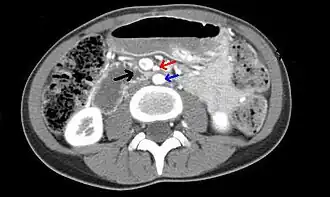

Tomografía computarizada de abdomen y pelvis que muestra compresión duodenal (flecha negra) por la arteria mesentérica superior(flecha roja) y la aorta abdominal (flecha azul).

El síndrome de la arteria mesentérica superior o síndrome de Wilkie es una entidad poco frecuente causada por la compresión de la tercera porción del duodeno entre de la arteria aorta y la arteria mesentérica superior causando dolor y una obstrucción abdominal alta.[1]